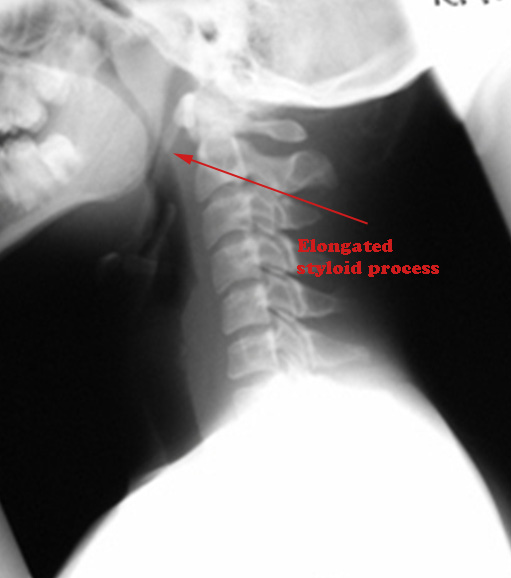

X-ray skull lateral view showing elongated styloid process

Classically the normal styloid process is about 1 inch long. It is generally accepted as elongated if the length exceeds 4 cms. Elongated styloid process can be unilateral or bilateral. Orothopantomograms are helpful in identifying this condition. It should be remembered that ony 4% of patients with elongated styloid process are symptomatic.